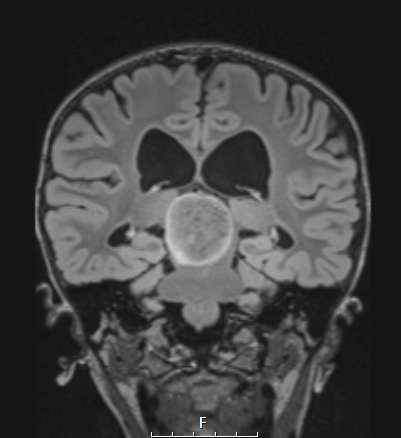

A large peripherally hyperintense tectal mass is shown in coronal view in this FLAIR scans.